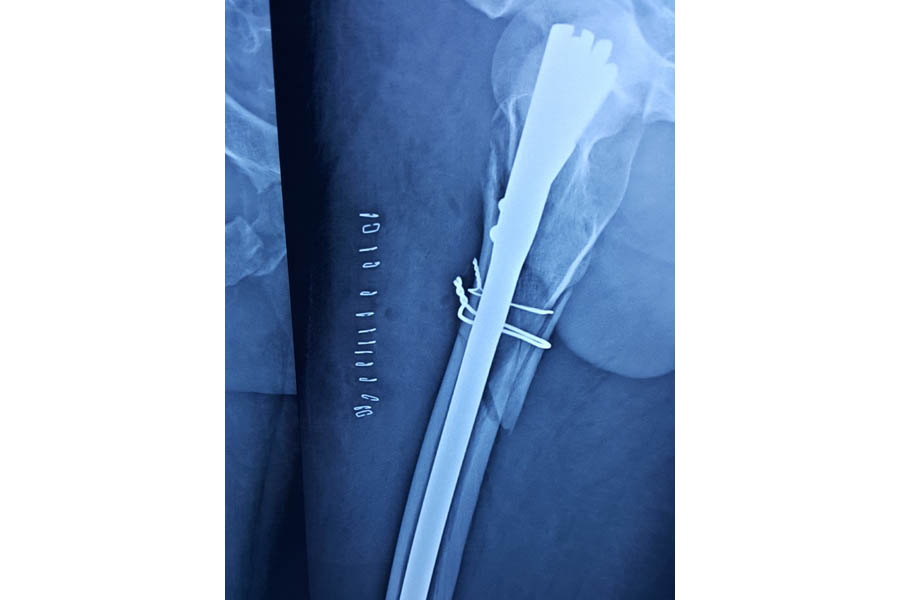

Trauma

Case 1